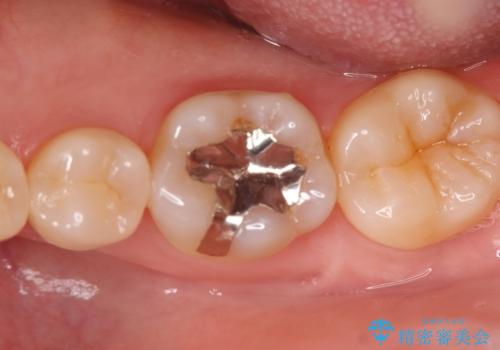

銀歯の下の虫歯|オールセラミッククラウン

担当医 河野豊嘉

奥歯に虫歯があると言われた セラミッククラウンでキレイで長持ちする歯へ

担当医 榊原康平